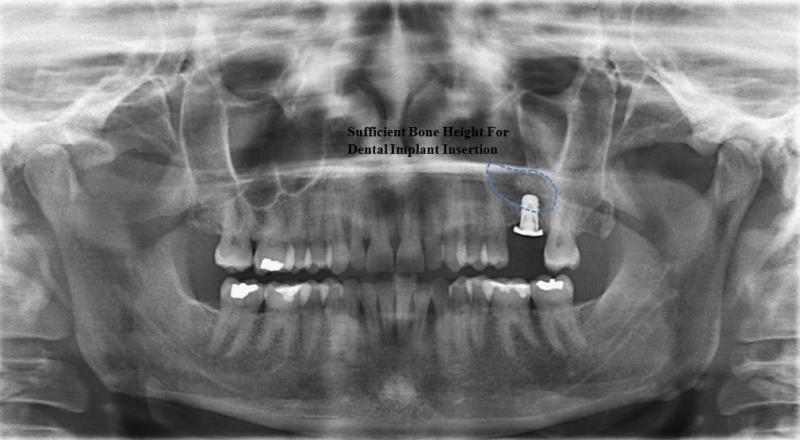

Surgery to insert osseo-integrated dental implants and Maxillofacial implants for attaching craniofacial prostheses (See Images Below)